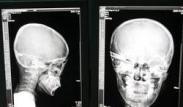

正常成人如超過1.96kPa(200mmH2O)即為顱內壓增高。顱內占位性病變、顱內感染性疾病、顱腦損傷、腦缺氧等均可造成顱內高壓。

- 常見癥狀:頻繁嘔吐或者噴射狀嘔吐、頭痛、視乳頭水腫、昏睡、昏迷